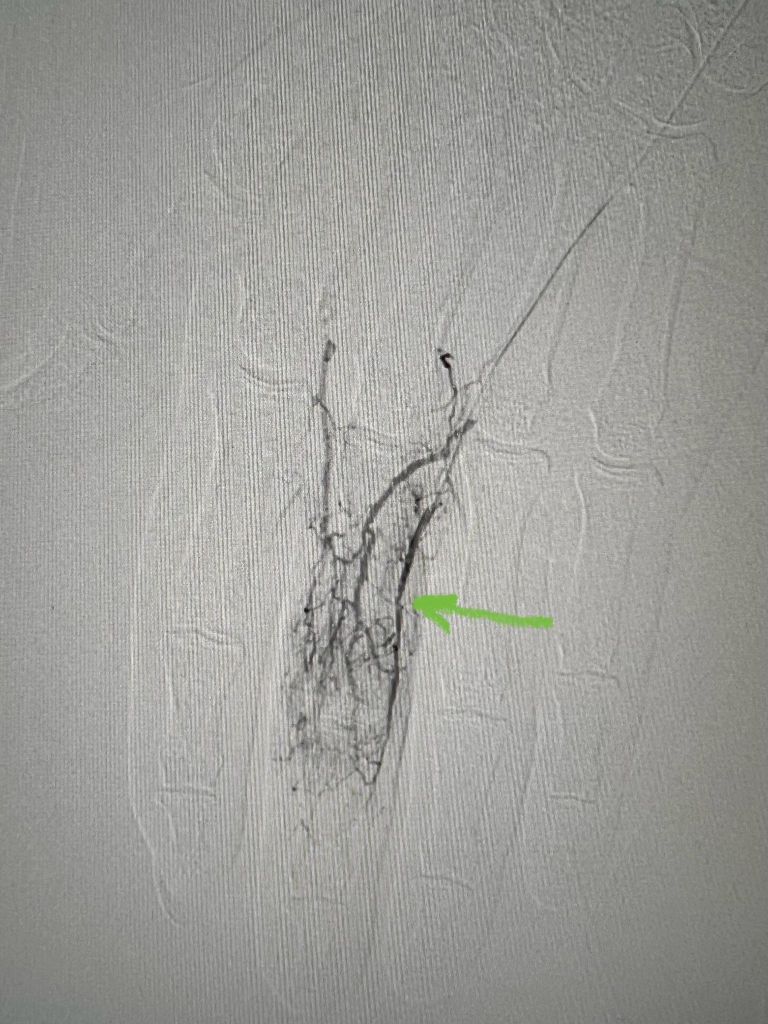

Similar to LDL-cholesterol, the cholesterol found in Lp(a) can accumulate in the walls of your blood vessels. The higher your Lp(a) level, the greater the likelihood of this occurring. These deposits of cholesterol, known as plaques, have the potential to reduce blood flow to various organs such as the heart, brain, kidneys, lungs, legs, and other parts of the body. Over time, plaques can gradually grow or suddenly rupture, obstructing blood vessels and resulting in heart attacks or strokes.Lp(a) has the potential to induce heightened clotting, which in turn can result in the formation of blockages in blood vessels at a rapid pace. Lp(a) promotes inflammation which increases the likelihood that plaques will rupture.(2) Additionally, heightened levels of Lp(a) can contribute to the development of aortic stenosis, a condition characterized by the narrowing of the aortic valve due to inflammation. This chronic inflammation can lead to the accumulation of calcium on the valve, resulting in stiffness. As a consequence, blood flow may be compromised if the valve fails to open fully. In certain instances, individuals with aortic stenosis may require surgical intervention or a procedure to replace the affected aortic valve.(2) Convincing evidence has emerged from pathophysiological, epidemiological, and genetic studies on the causality of high serum lipoprotein(a) (Lp(a)) levels as a potent risk factor for coronary heart disease (CHD), ischemic stroke, peripheral artery disease, heart failure, calcific aortic valve stenosis (CAVS), mitral valve stenosis, and retinopathy in patients with diabetes.(14) (Fig. 1)

Fig. 1: The pathogenicity of lipoprotein(a). (Source: Koutsogianni et al, 2023)